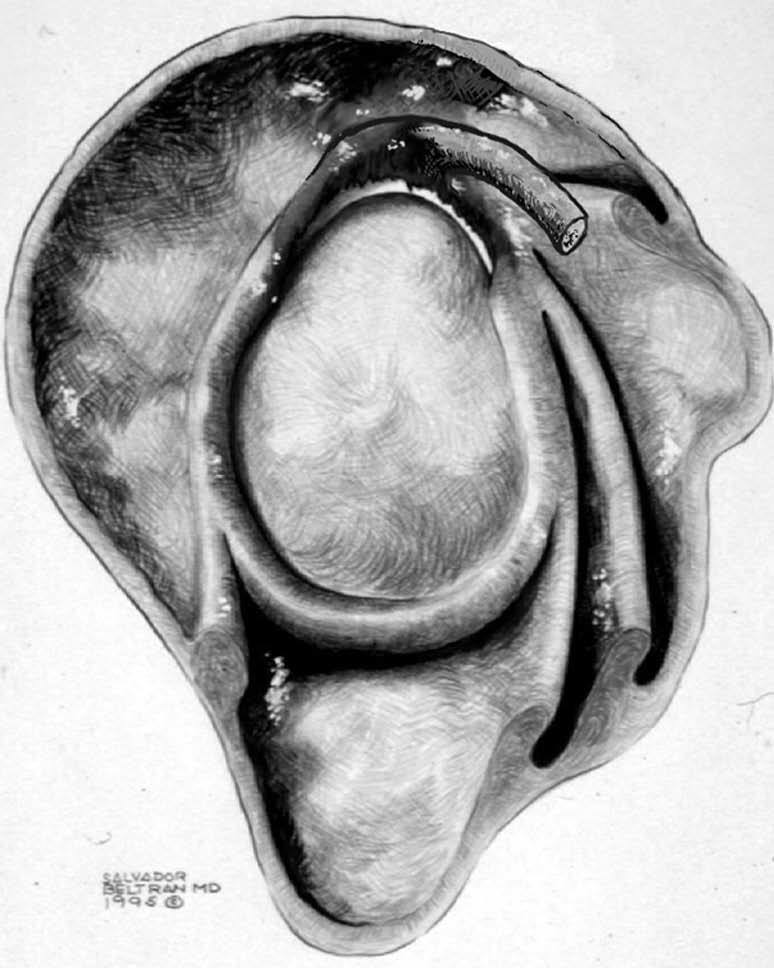

POLPSA (posterior labral periosteal sleeve avulsion)

Esta lesión se asemeja a la ALPSA, pero ocurre en el borde glenoideo posterior. El LG se halla desplazado hacia dentro y por detrás del borde glenoideo posterior. El mecanismo de producción del POLPSA es una dislocación posterior, y por tanto se puede encontrar también un Hill Sachs invertido19 (fig. 14).

. Artrorresonancia axial T1 con supresión grasa donde se observa una rotura del labio glenoideo posterior con desplazamiento posteromedial (flecha). Nótese la situación del labio glenoideo en comparación con una rotura sencilla, no desplazada, que se observa en la figura 13. Obsérvese la presencia de una lesión de Hill-Sachs invertida (cabezas de flecha), en relación con una dislocación posterior con reducción.Lesión de Bennett